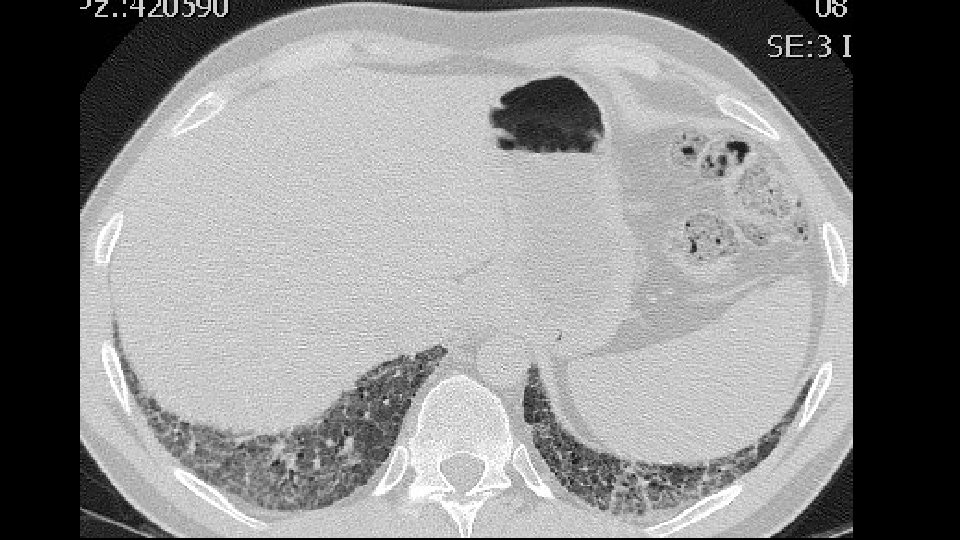

ADDITIONAL HISTORY Patient underwent five cycles of cyclophosphamide (750 mg/mq) EKG and LAB tests: Normal/negative Dyspnea persisted CT scan was repeated seven months later followed by a VATS B

Increase of coarseness

Increase of cysts in the contest of reticulation a ground glass attenuation

Progressive decrease of subpleural sparing

VATS Bx: Fibrosis with honeycombing, in some areas patchy